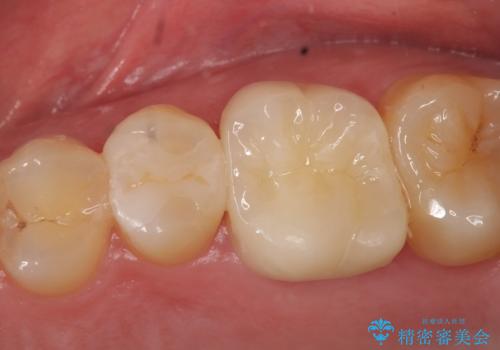

- 左上の奥歯が痛んでものを食べられないといらっしゃった方の症例です。

左上6は虫歯を除去後、神経症状がないことを確認し、オールセラミッククラウンによる補綴を行いました。

左上5は古い樹脂と虫歯を除去後、セラミックインレーによる修復を行いました。

今回用いたオールセラミッククラウンはジルコニアフレームという白い素材の上にセラミックを盛っているため、審美性が非常に高いのが特徴です。

また、ジルコニアは人工ダイヤモンドの材料にも使われているほど高い強度を持っており、そのためオールセラミッククラウンは審美性だけでなく、奥歯やブリッジの補綴も可能とするクラウンです。